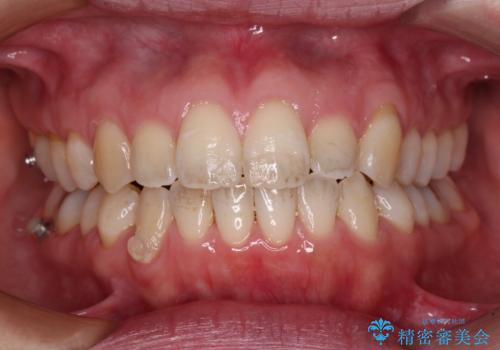

受け口傾向の歯並びをインビザラインで改善

- 受け口傾向でクロスバイトの前歯を治したいとのことで来院された患者様です。

下顎骨が若干左側に変位していたため、右側にアンカースクリューを使用し、積極的に移動させながらインビザラインにて矯正治療を行うこととしました。

インビザラインによる矯正治療は、受け口傾向の治療に非常に適した方法であり、事前にシミュレーションに沿って治療を進めることできます。

今回の治療では骨格的な偏位があったためアンカースクリューを使用し、より確率の高い治療を行うことができました。